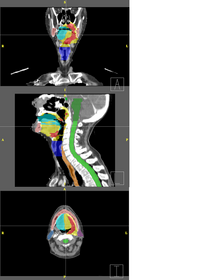

Adaptive Radiotherapy for head, neck and thoraxWe proposed an algorithm to include prior knowledge in previously segmented anatomical structures to help in the segmentation of the next structure. This will add enough prior information to allow the Graph Cuts algorithm to segment structures with fuzzy boundaries. More... New: I. Kolesov, V. Mohan, G. Sharp and A. Tannenbaum. Graph Cut Segmentation Based on Local Statistics Using Anatomical Landmarks. SPIE Medical Imaging 2010 (in submission).